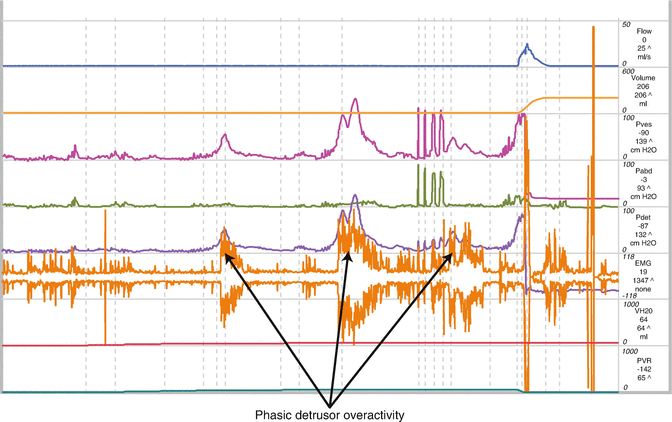

4 Detrusor Overactivity With Leak Download Scientific Diagram